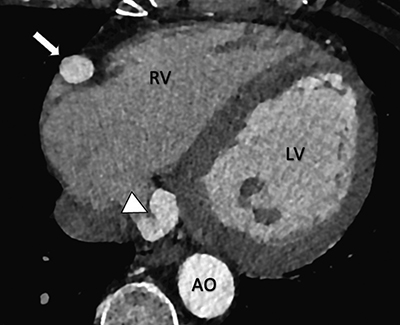

Figure 3

Cardiac CT-angiography reveals a coronary artery-to-coronary sinus fistula (white arrowhead). Note the dilation of the right coronary artery (white arrow). Axial view.